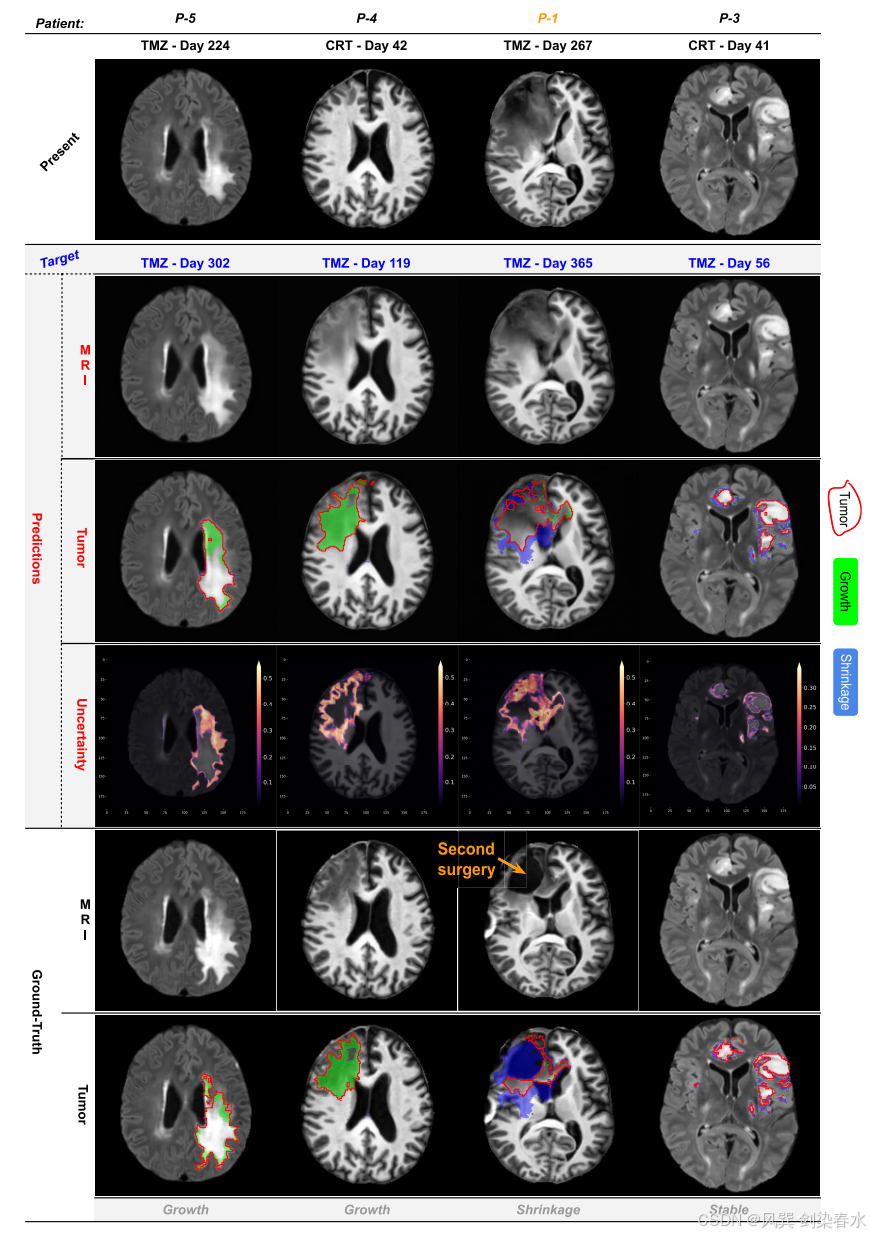

Figure 3 | 内部测试病例的定性预测示例:从上至下,展示了当前(源)MRI 图像,其中包含特定治疗日的痕迹;目标(未来)治疗日;预测结果,包括生成的MRI图像、肿瘤掩模和不确定性图;以及真实情况。该方法能够模拟稳定和进展中的肿瘤,这些肿瘤在不同部位可能有生长或缩小的情况。值得注意的是,P-1 接受了第二次手术治疗,这超出了我们模型设计处理的治疗类型范围;